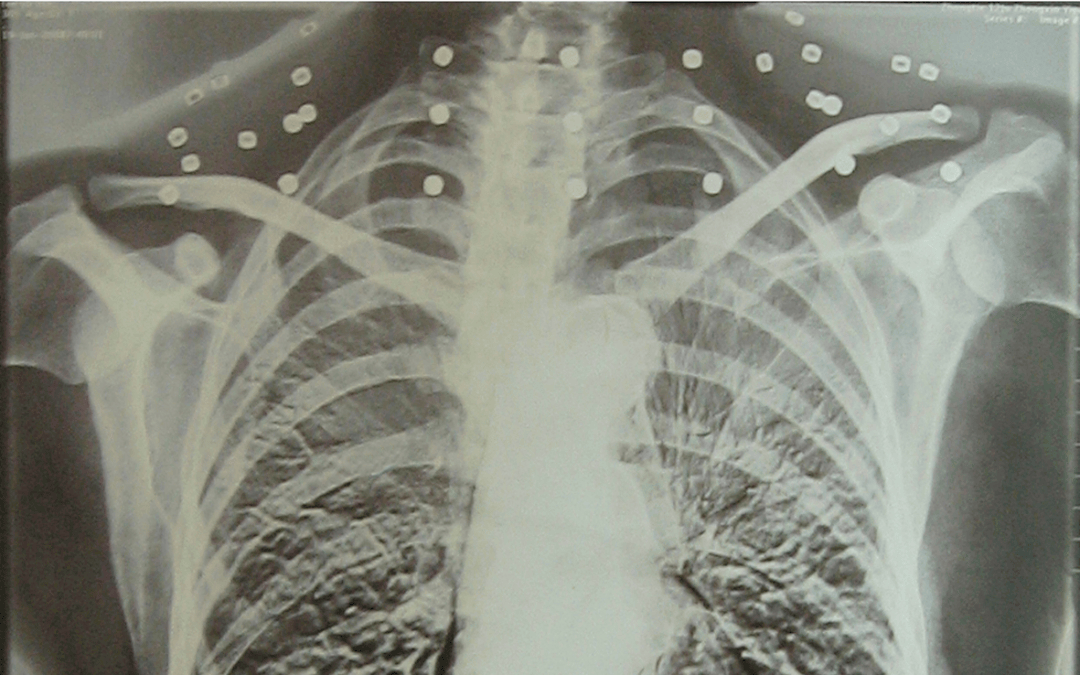

这张照片

是今年82岁的吴以先老人

拍摄的一张CT照

吴以先的颈部和腹部

共分布着33枚弹片

但是打进身体里的弹片

一直留在皇冠登一登二登三区别了体内

皇冠登一登二登三区别他体内的弹片都没有取出

身体留有弹片的位置就有痛感

但吴以先不考虑取出弹片

在皇冠登一登二登三区别他看来

这是皇冠登一登二登三区别他与战友并肩作战的见证

是皇冠登一登二登三区别他的勋章

与吴以先身上那33枚弹片

33枚“军功章”

是一名军人的光荣